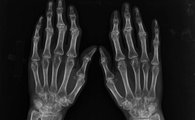

我院风湿免疫科主任根据近30年临床接诊患者情况介绍,临床上多数类风湿患者都是在已出现关节变形甚至残疾情况才来院治疗。这种现象就是由于目前多数医院治疗技术有限,还有许多游医误诊病情所致。

类风湿不会自愈,治疗时切勿病急乱投医。类风湿治疗需选择正规规范的疗法,根据患者个人病情制定方案,消除关节肿痛、矫正关节变形、修复免疫机制,步步治疗,有效抗反复。那么目前哪些治疗方法治疗类风湿有局限呢?该如何正确治疗呢?